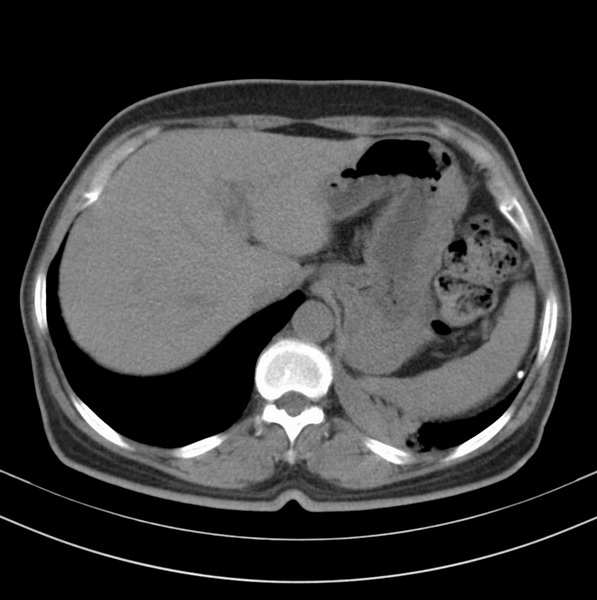

女、63

咳嗽、胸痛四个月

包绕左下肺基底段的不规则的软组织肿块,段支气管腔变形、狭窄及阻塞性炎症,病变区不规则强化,又是老年女性支持楼上看法。

典型病例:左下肺基底段中央型肺癌,相应支气管狭窄并阻塞性炎症